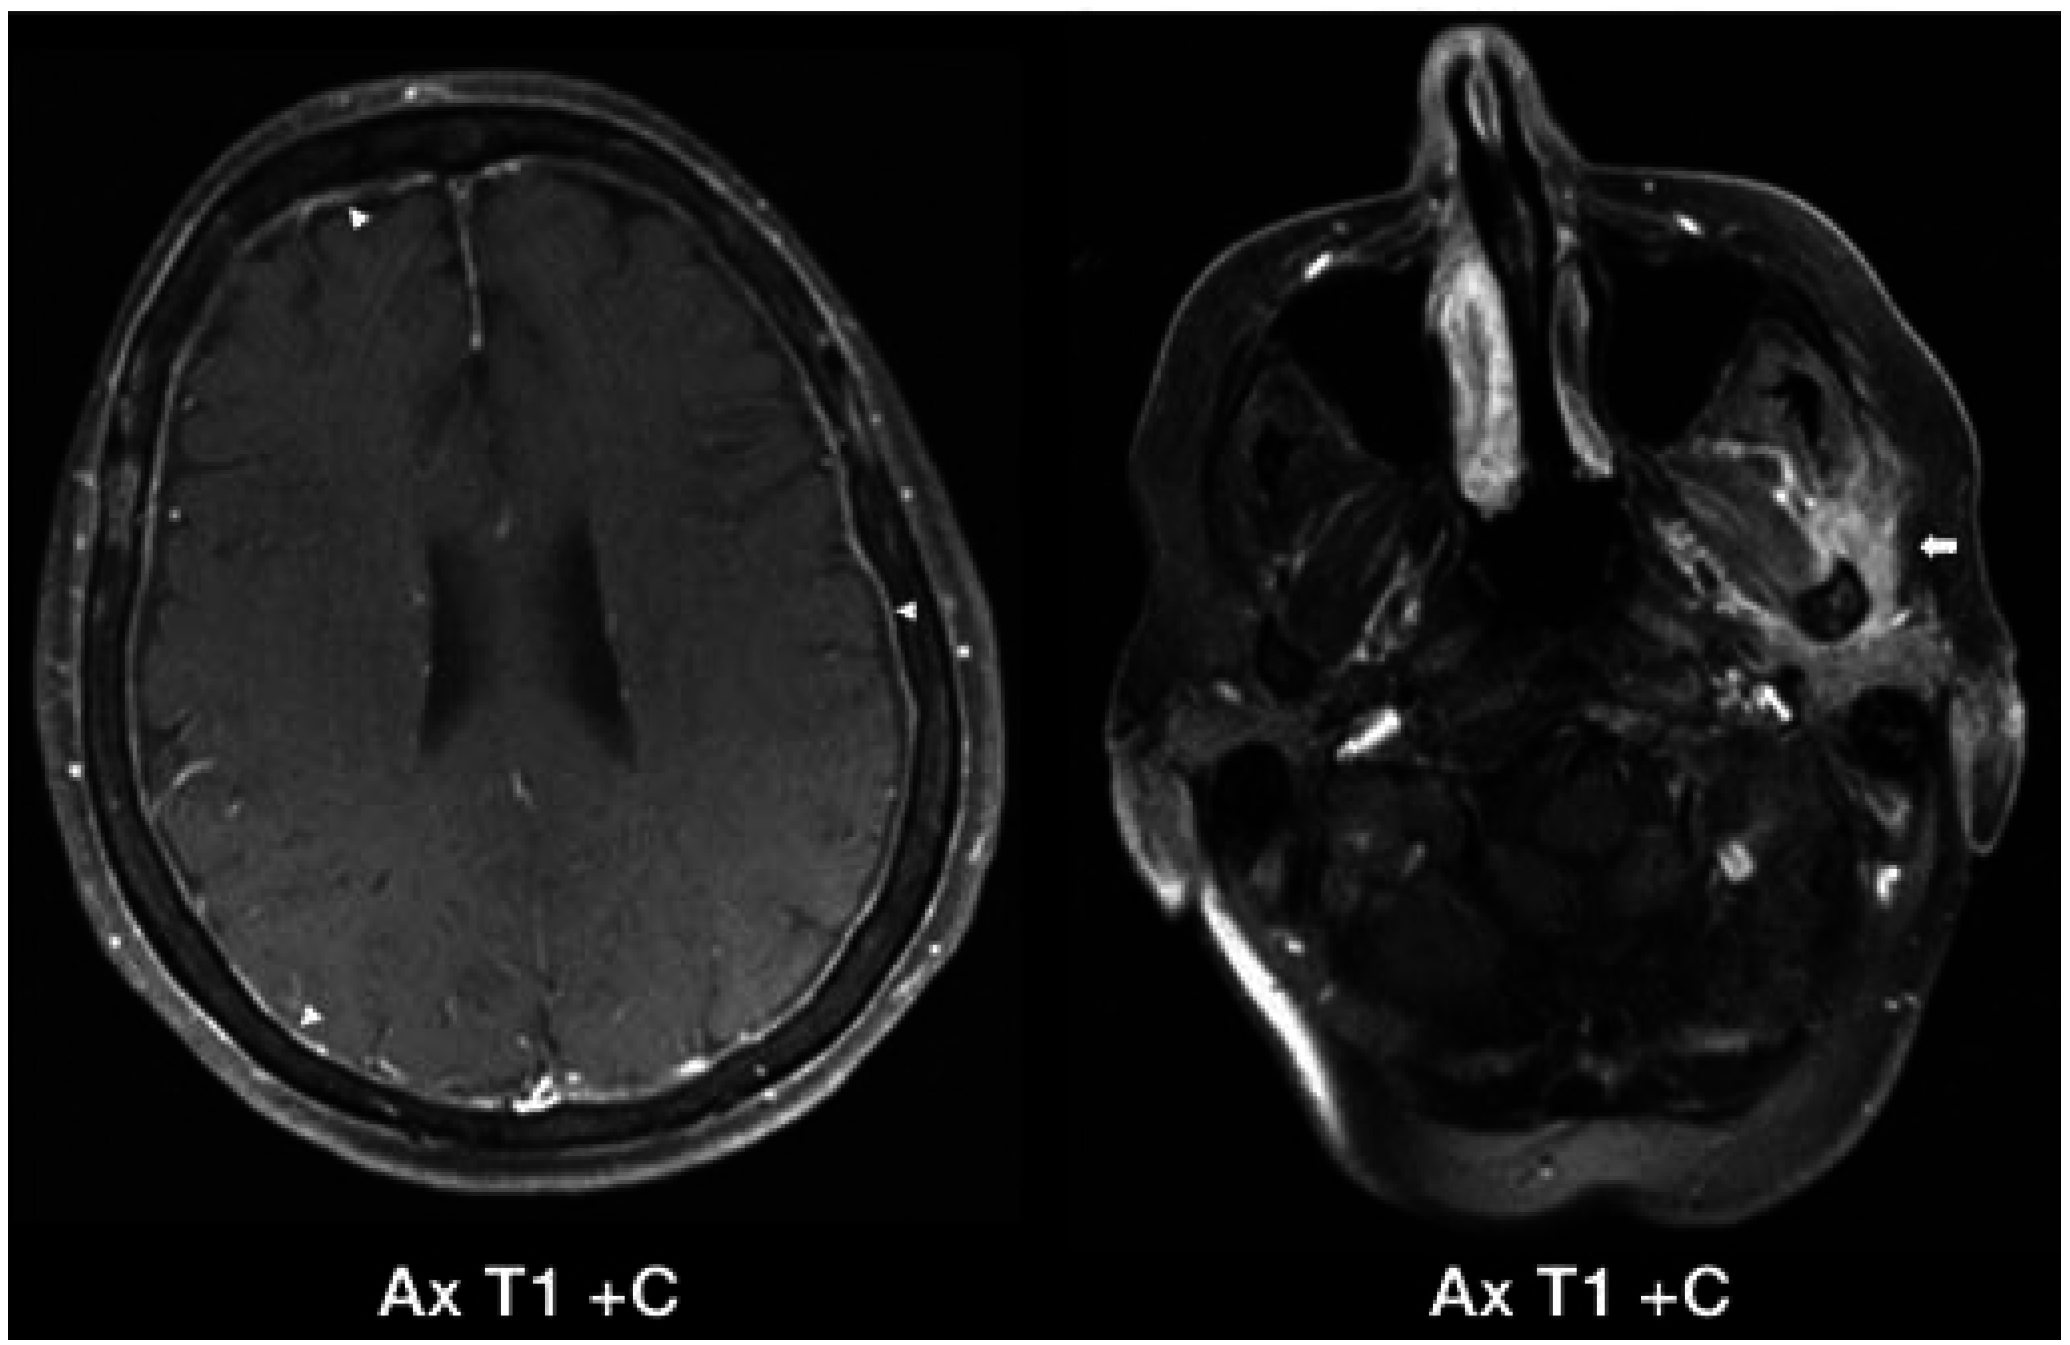

4. Authors’ Institution Case Reports